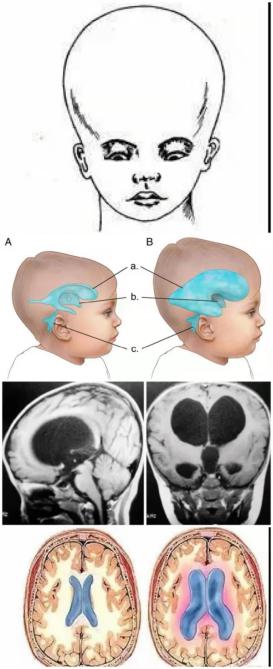

人脑被分为大脑、小脑和脑干,位于颅骨腔内。脑袋大说明颅骨腔也大,但是不见得脑体积一定大,因为在脑和颅骨之间充满了脑脊液,有可能存在脑积水情况。脑积水患儿会表现为“大头娃娃”,这会严重影响患儿的发育及智力水平。

对于脑积水的人来说,长时间的压迫脑组织,导致神经元和胶质细胞凋亡、神经突出减少,进而导致脑萎缩发生,进而发展成脑积水性痴呆。